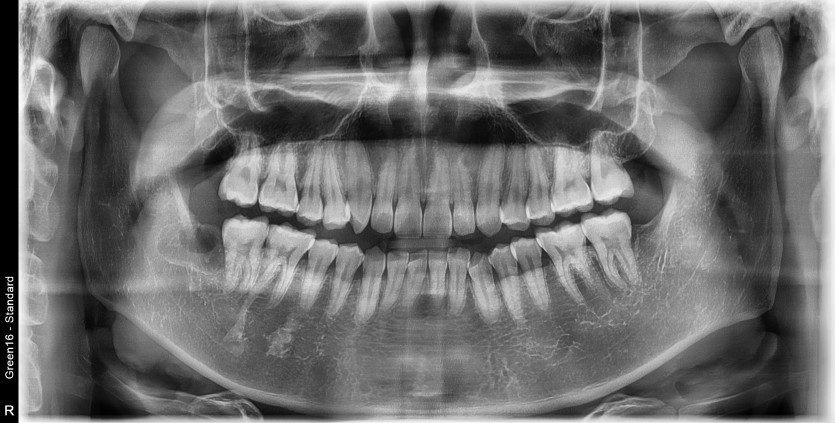

#18,48 사랑니 발치

구강 외과 전문의가 당일 발치했습니다.